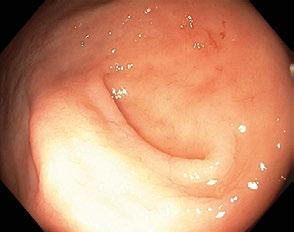

Obr. 1.1 Ampula rekta s příčnými rektálními řasami